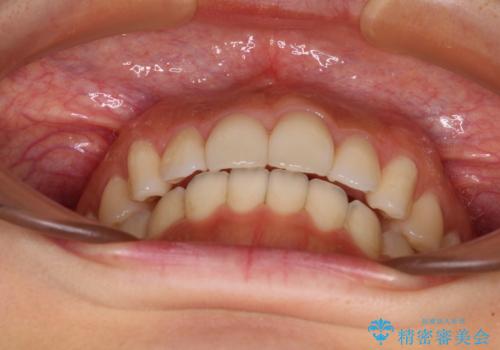

- 飛び出した前歯と口元の突出感を気にして来院された患者様です。

奥歯の咬み合わせを見ると、上顎が下顎に対して相対的に前方にありました。

口元の突出感を改善するためには、上顎臼歯を後方に移動させた咬み合わせにする必要があります。

インビザライン単体で改善することも可能ですが、達成する可能性が高くないため、カリエールディスタライザーという補助装置を併用して、より確実性を上げることとしました。

奥歯の咬み合わせを改善しながら、並行してインビザラインで歯列を整えることとしました。